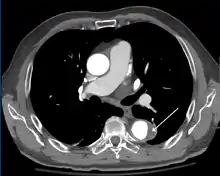

Computed tomography

Computed tomography angiography is a fast, noninvasive test that gives an accurate three-dimensional view of the aorta. These images are produced by taking rapid, thin-cut slices of the chest and abdomen, and combining them in the computer to create cross-sectional slices. To delineate the aorta to the accuracy necessary to make the proper diagnosis, an iodinated contrast material is injected into a peripheral vein. Contrast is injected and the scan performed using a bolus tracking method. This type of scan is timed to an injection to capture the contrast as it enters the aorta. The scan then follows the contrast as it flows through the vessel. It has a sensitivity of 96 to 100% and a specificity of 96 to 100%. Disadvantages include the need for iodinated contrast material and the inability to diagnose the site of the intimal tear.

CT with contrast demonstrating aneurysmal dilation and a dissection of the ascending aorta (type A Stanford)

Chest CT with descending (type B Stanford) aortic dissection (red circle)

Type A dissection with pericardial effusion as a result.